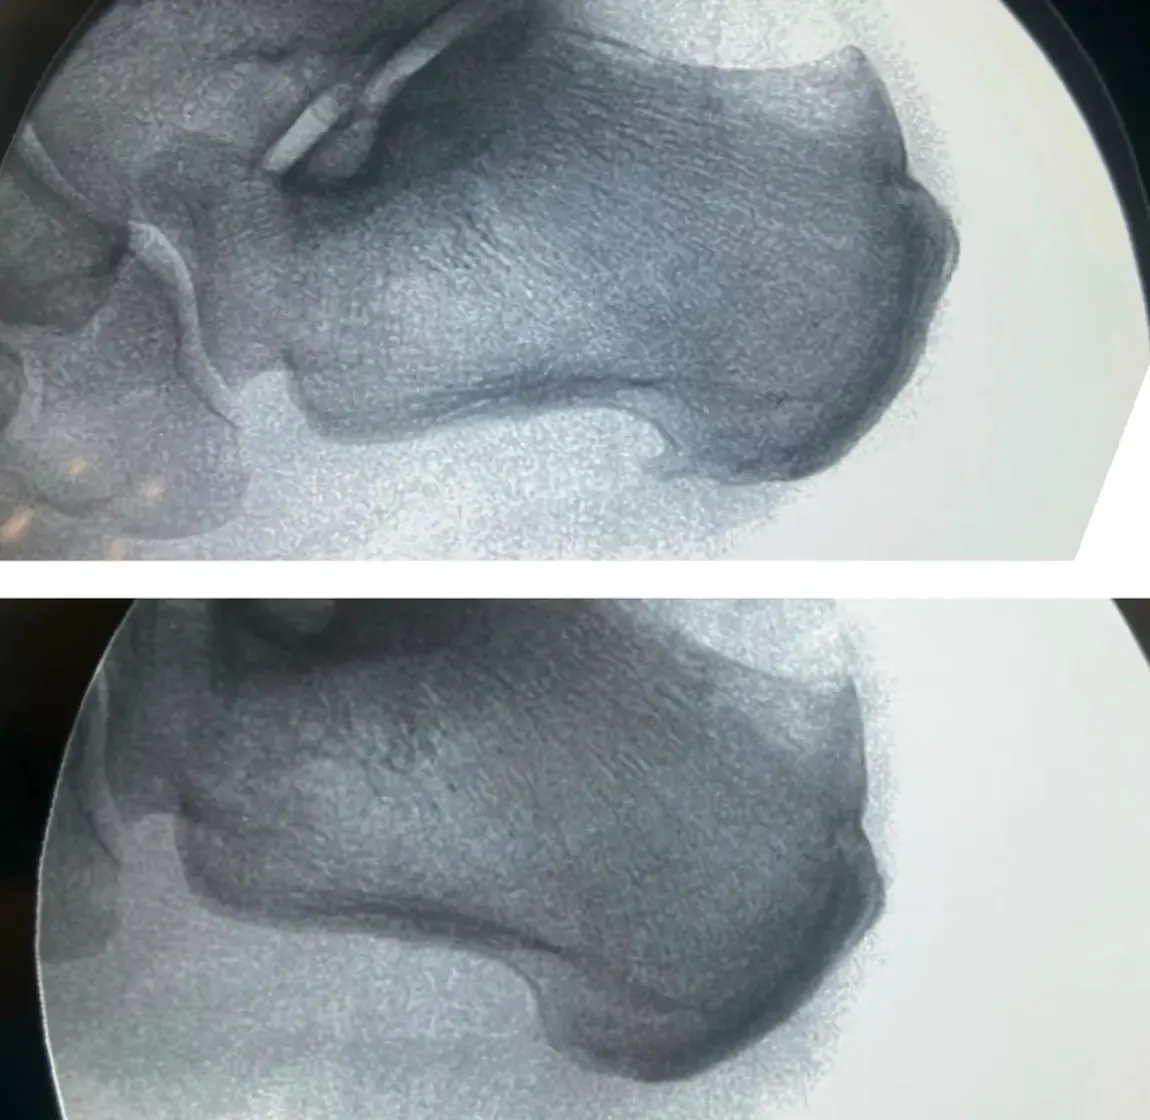

La Radiografía que lo Complicó Todo

Como muchos pacientes con dolor de talón, María acudió primero a otro profesional que le realizó una radiografía. Y ahí estaba: un espolón calcáneo visible como una pequeña espícula ósea.

“El espolón es lo que me está matando, ¿verdad? Por eso me duele tanto”, preguntó esperando confirmación.

María llegó a nuestro Centro Podológico Henao convencida de que el espolón era el culpable. Había incluso buscado en internet sobre “cirugía de espolón calcáneo”. Pero nosotros teníamos nuestras dudas.

Las radiografías muestran huesos, pero no pueden ver tejidos blandos como bursas o tendones. Por eso la ecografía podológica es fundamental en estos casos.

- El espolón calcáneo visible: presente, sí, pero sin signos inflamatorios alrededor, como un espectador silencioso

¿Y el espolón? Seguía ahí, en su radiografía. Pero María ya ni se acordaba de él.

- El espolón calcáneo raramente es la causa directa del dolor. En el caso de María, era un hallazgo radiológico incidental que distrajo la atención del verdadero problema.